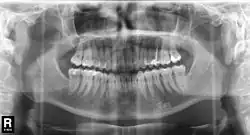

En 1934, le Japonais Hisatugu Numata met au point le premier appareil à panoramiques X dentaires. La mise au point de l'appareil intraoral, où le tube émetteur se trouve à l'intérieur de la bouche et le film à l'extérieur suit. En parallèle, Horst Beger, de Dresde, en 1943 et Walter Ott, dentiste suisse, en 1946 mettent au point les appareils Panoramix (Koch & Sterzel), Status X (Siemens) und Oralix (Philips)[129]. Le Finlandais Yrjö Veli Paatero (1901–1963) continue à mettre au point la technique et donne à l'appareil le nom de Parabolographie, puis de Pantomographie en 1950, et enfin sur la suggestion du Japonais Eiko Sairenji le nom Orthopantomographie en 1958[130],[131],[132]. Le premier de ces appareils est distribué en 1961 sous le nom de Panorex par la firme S.S. White[133]. Les tubes émetteurs et le film y tournent de façon synchrone autour de la tête du patient. À la fin des années 1980, les appareils panoramiques intraoraux sont abandonnés définitivement, parce que la dose de rayonnement par le tube en contact avec la langue et la muqueuse buccale se trouve trop élevée.